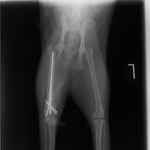

他院にて左大腿骨遠位の成長板骨折(salter-harrisⅠ型)が認められており、治療相談を目的として来院。当院にて、キルシュナーワイヤーを用いたピンニングにより骨折部位の整復を行いました。術後の経過は良好で、現在も経過観察中です。

術後レントゲン

機器

Arthrex社のターゲティングデバイスを用いてピンニングの位置を調整することで、確実な固定を行っています。当院ではこの手術器具以外にも、人の手術にも使用される様々な器具を導入し、手術精度を高め、また医療メーカーと新しい器具の開発、試作にも取り組んでおります。